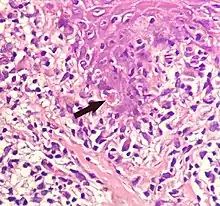

A sunburn cell is a keratinocyte with a pyknotic nucleus and eosinophilic cytoplasm that appears after exposure to UVC or UVB radiation or UVA in the presence of psoralens. It shows premature and abnormal keratinization, and has been described as an example of apoptosis.[33][34]

A Civatte body (named after the French dermatologist Achille Civatte, 1877–1956)[36] is a damaged basal keratinocyte that has undergone apoptosis, and consist largely of keratin intermediate filaments, and are almost invariably covered with immunoglobulins, mainly IgM.[37] Civatte bodies are characteristically found in skin lesions of various dermatoses, particularly lichen planus and discoid lupus erythematosus.[37] They may also be found in graft-versus-host disease, adverse drug reactions, inflammatory keratosis (such as lichenoid actinic keratosis and lichen planus-like keratosis), erythema multiforme, bullous pemphigoid, eczema, lichen planopilaris, febrile neutrophilic dermatosis, toxic epidermal necrolysis, herpes simplex and varicella zoster lesions, dermatitis herpetiformis, porphyria cutanea tarda, sarcoidosis, subcorneal pustular dermatosis, transient acantholytic dermatosis and epidermolytic hyperkeratosis.[37]